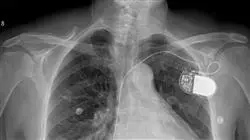

La Radiología torácica estudia gran variedad de patologías con elevada prevalencia en nuestra sociedad. El diagnóstico radiológico es fundamental en el manejo del paciente y, en gran parte de ellos, es la primera prueba complementaria realizada. Los recientes avances tecnológicos han permitido la realización de estudios angiográficos por vía venosa para la detección de tromboembolismo pulmonar y, añadido a las adquisiciones con gran resolución temporal, el estudio de la patología coronaria.

El programa está orientado a actualizar al profesional en el estudio de las áreas más importantes del tórax que aborda la patología del espacio aéreo, enfermedades intersticiales, patología pleural, cáncer de pulmón, evaluación del mediastino, traumatismo torácico o patología vascular aórtica y cardíaca.

- Imágenes reales en alta resolución, tanto de patologías del tórax como de sus pruebas diagnósticas de imagen

1.10. Imagen cardíaca